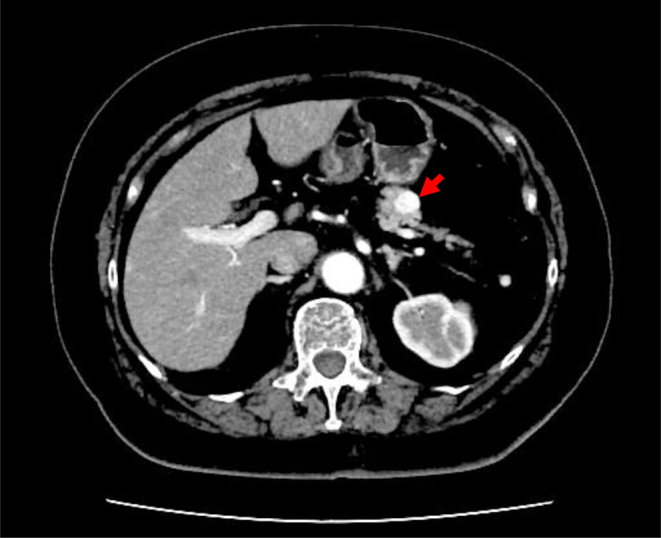

Summary: An 89-year-old woman presented with a 6-year history of occasional episodes of impaired consciousness that were relieved by ingestion of a snack. Three months before presenting to our hospital, she had been hospitalized in a local hospital with subdural hematoma caused by a head contusion, where previously unrecognized hypoglycemia was discovered. Fasting plasma glucose concentration was 37 mg/dL, with a relatively high serum level of insulin (34.9 µU/mL). Computed tomography showed a 14 mm hyperenhancing tumor in the tail of the pancreas and she was referred to our hospital for further investigation. A prolonged fasting test revealed the plasma glucose concentration reduced to 43 mg/dL (2.4 mmol/L) at 8 h after the last meal. Serum insulin, proinsulin, and C-peptide concentrations were 21.1 µU/mL, 16.9 pmol/L, and 2.72 ng/mL, respectively. Subsequent intravenous administration of 1 mg of glucagon increased the plasma glucose concentration to 76 mg/dL (4.2 mmol/L). Moreover, the insulin-to-C-peptide molar ratio was 0.14. These data indicated the presence of insulinoma. Interestingly, serum anti-insulin antibodies were elevated (21.1 U/mL), although she had no history of taking exogenous insulin injection, alpha lipoic acid, or sulfhydryl group-containing agents. Human leukocyte antigen (HLA) typing revealed HLA-DRB1*0407 and HLA-DRB1*1405 alleles. Treatment with diazoxide prevented hypoglycemia, but was discontinued due to weight gain and leg edema. Elevated serum anti-insulin antibodies persisted almost 1 year after the diagnosis of insulinoma. We present a rare case of insulinoma concomitant with serum anti-insulin antibodies.